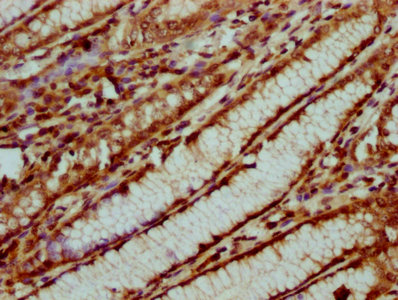

IHC (Immunohistochemistry)

(IHC image of AAA234919 diluted at 1:20 and staining in paraffin-embedded human gastric cancer performed on a Leica BondTM system. After dewaxing and hydration, antigen retrieval was mediated by high pressure in a citrate buffer (pH 6.0). Section was blocked with 10% normal goat serum 30min at RT. Then primary antibody (1% BSA) was incubated at 4 degree C overnight. The primary is detected by a biotinylated secondary antibody and visualized using an HRP conjugated SP system.)